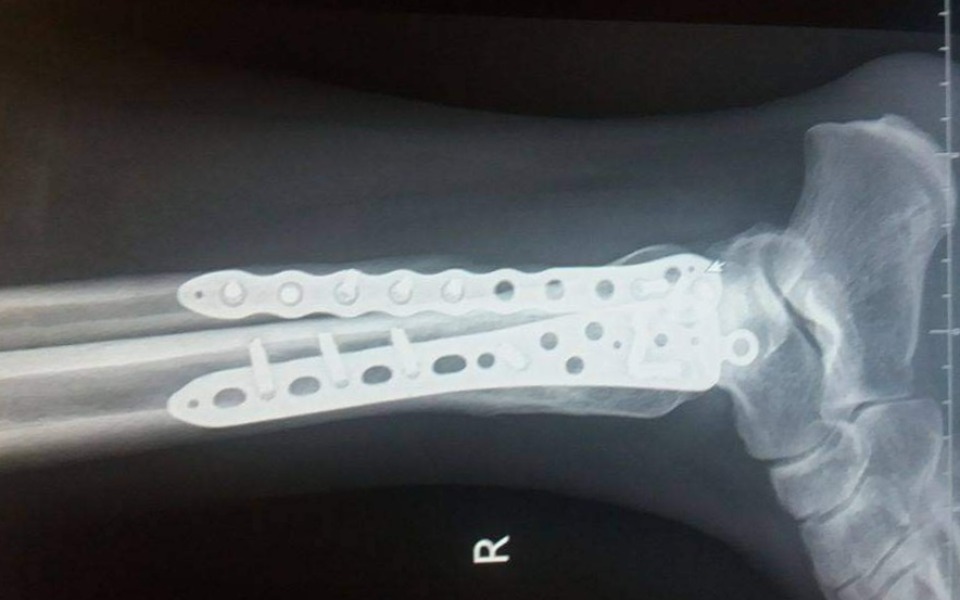

7 lat temu w wyniku wypadku doszło do poważnego złamania dwóch kosci w nodze, które zespolono dwiema płytami oraz 15 śrubami.